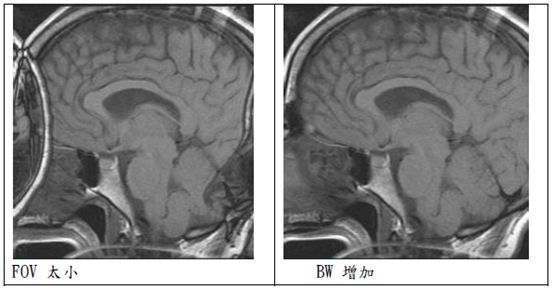

反摺假影(Aliasing artifact):

又稱wrap-around artifact

原理:對一個固定的FOV及梯度強度而言,最大頻率 fmax相對應於FOV的邊緣。一旦FOV外面部分感受到約2倍高的頻率,此較高頻率的FOV會包摺到較低頻率的FOV,而造成 aliasing artifacts

簡單說就是FOV太小,主要發生在相位編碼方向(phase encoding)

解決方法:

² 使用表面線圈:不要收到FOV之外的任何訊號,也可提高SNR

² 增加FOV:FOV增為兩倍來包括所有掃描的範圍,則可將aliasingnartifact消除。

² 增加取樣:增加取樣速率或者相位編碼數目

² 飽和脈衝:FOV外面的訊號飽和掉,降低aliasing artifact